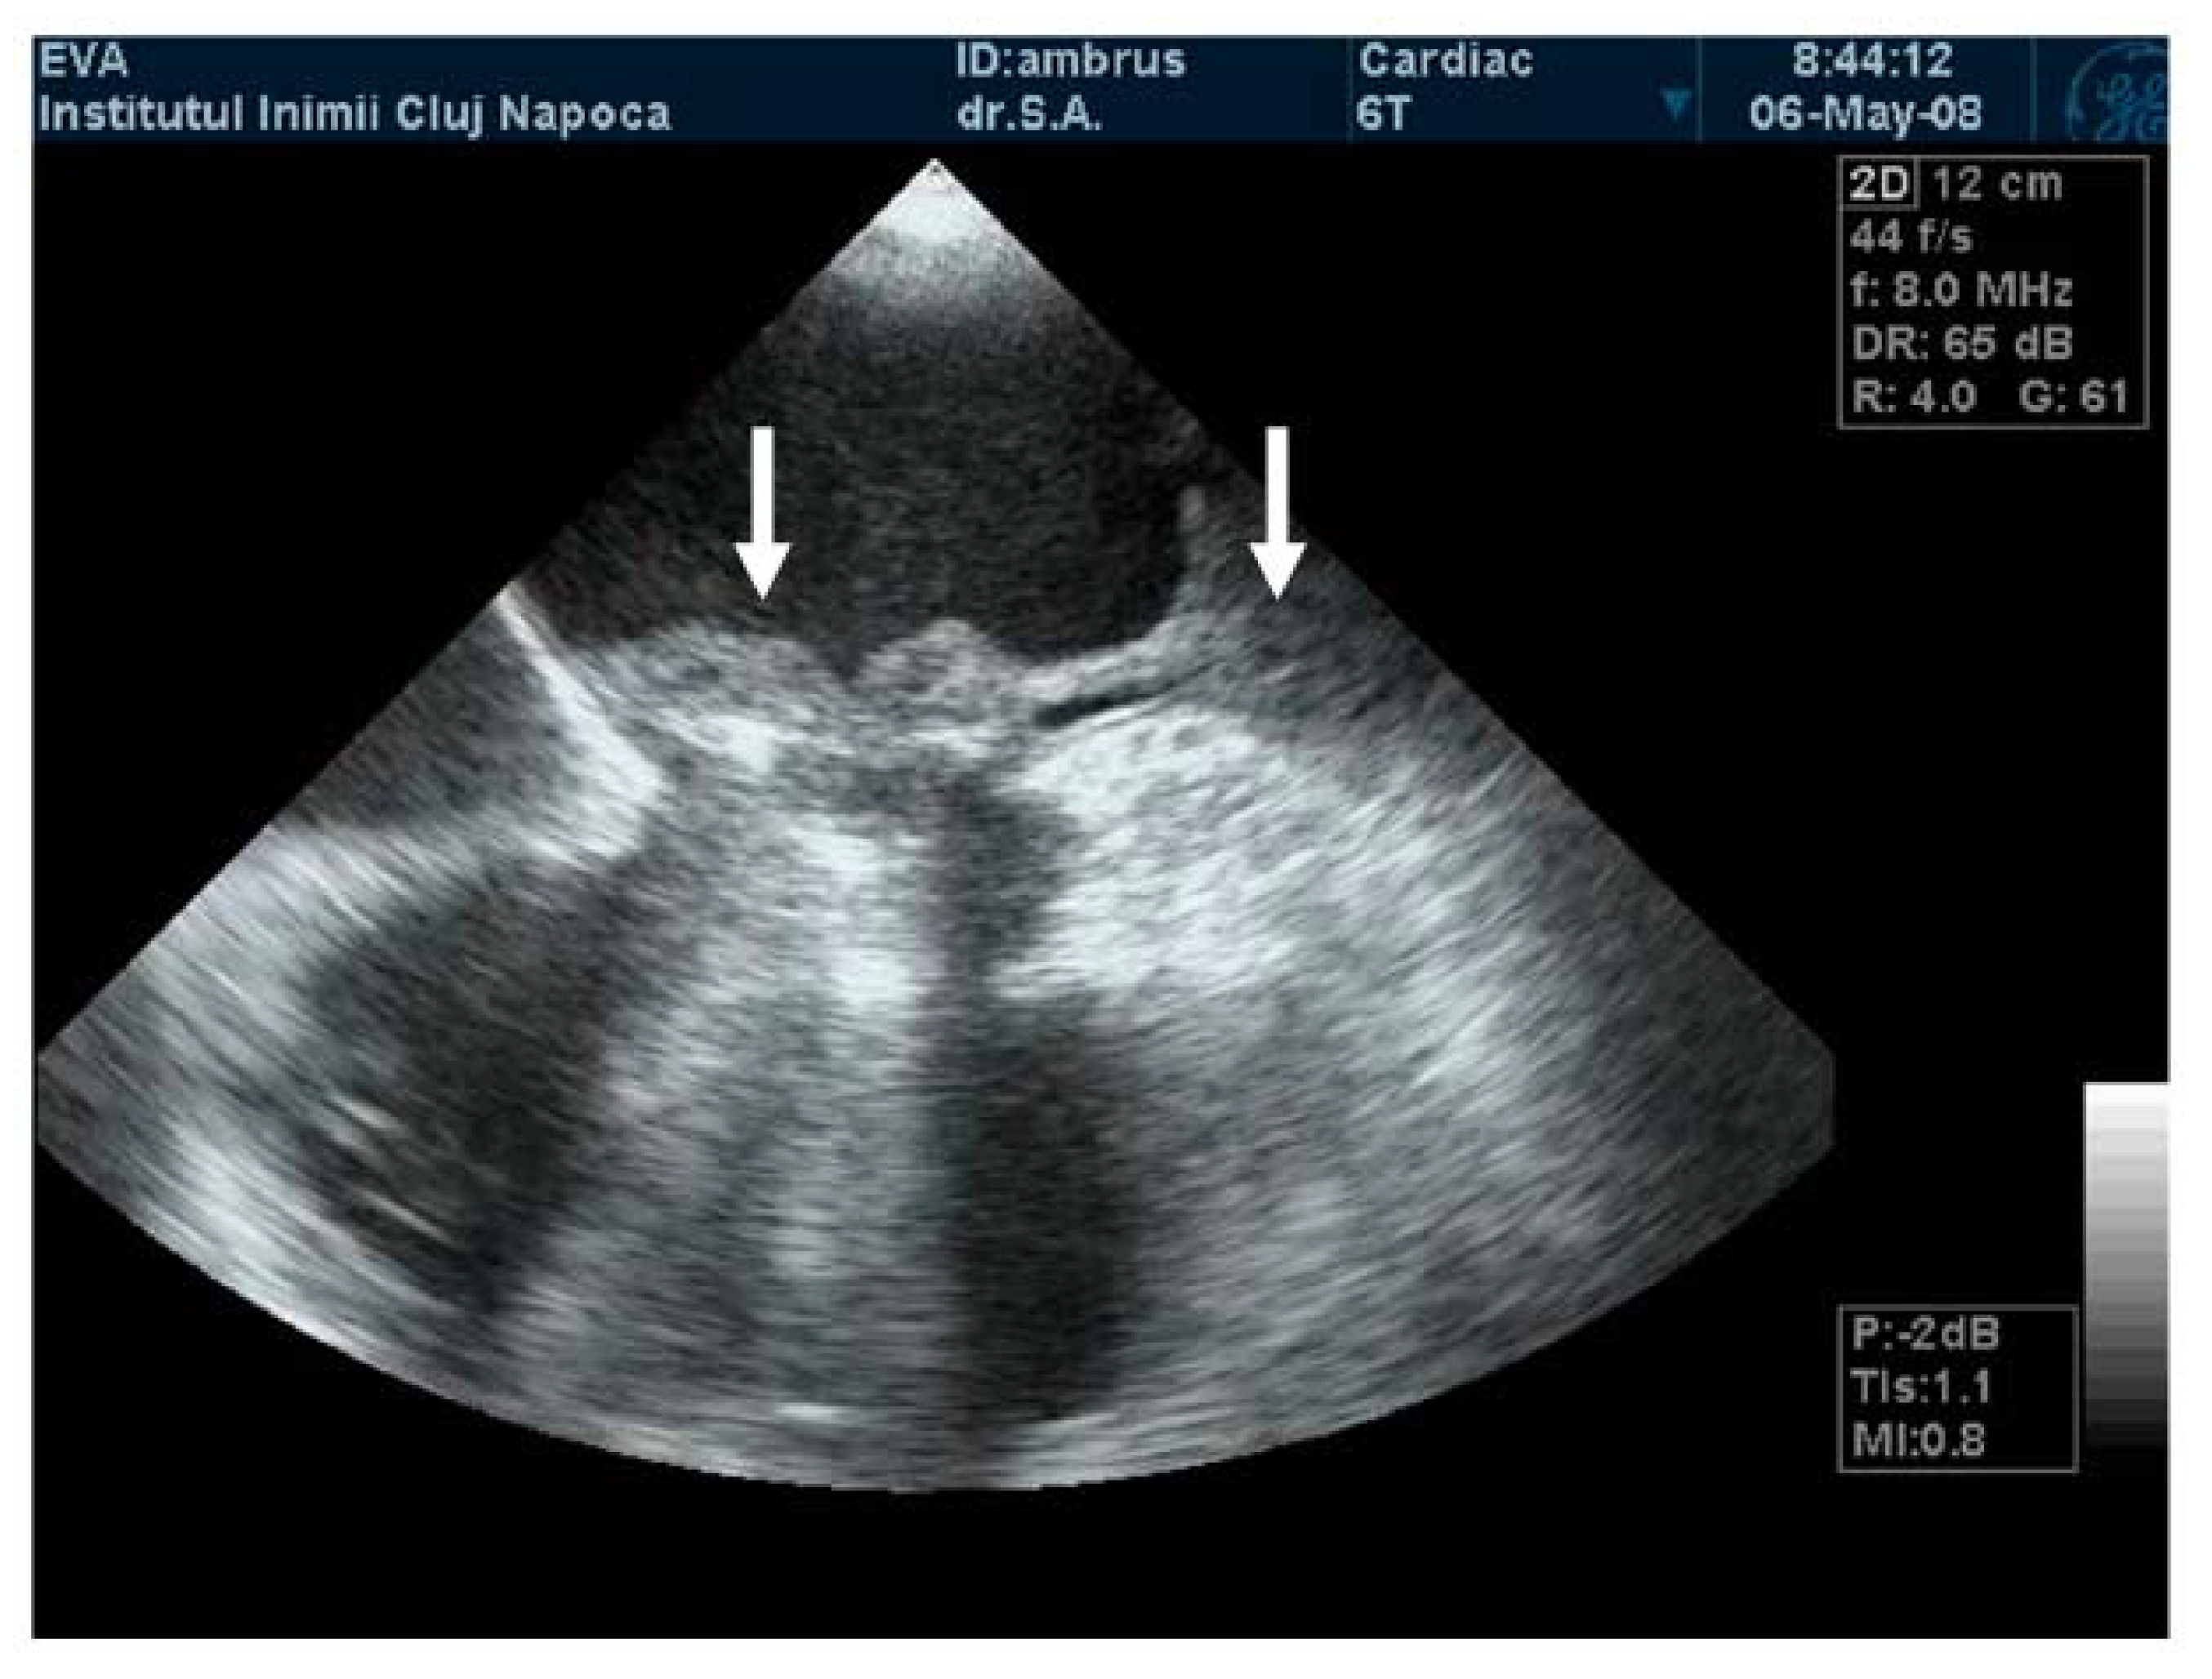

The mobility of the discs and the presence of pathological features such as thrombus, pannus, or vegetation are evaluated using bidimensional echocardiography. The thrombus can sometimes be difficult to visualize; in some cases, it appears as an echodense mass that is located on the discs and restricts their motion (Figure 2A) [17]. The colour Doppler flow quantification may reveal a turbulent flow above the valve or even the absence of colour flow through the prosthesis (Figure 2B). While 2D imaging leaves room for ambiguity in terms of thrombus localization in relation to the prosthesis, 3D images clearly reveal the relationship between them, as illustrated in the moving images of Video S1 (Supplementary Material). The evaluation of intracardiac masses suspected for thrombi using pulsed wave (PW) tissue Doppler imaging (TDI) might be an improvement over visual assessment, as it provides a more precise definition of mass mobility [18,19].

Figure 2.

(A) TTE. Prosthetic mitral valve PLAX thrombus on the disc left atrial side (arrow). (B) TTE. Colour Doppler turbulent flow above the prosthesis (arrow).